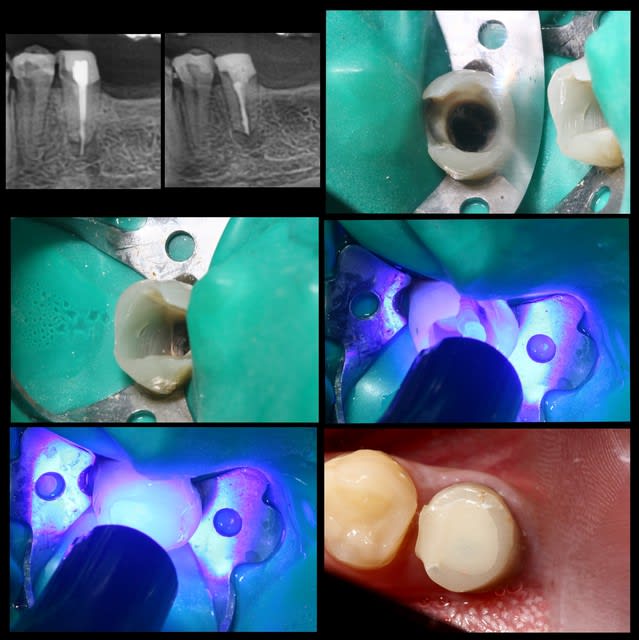

Pour exposer mes propos, cas de ce matin.

Endo galère à reprendre, reconstruction compo pré endo.

Une fois l'endo terminée, j'agrandi ma cavité pour ne garder en périphérie que l'épaisseur de la futur céram.

Je fais ensuite mon protocole adhésif avec tenon fibré.

A la dépose il reste à préparer, le compo pré endo sera tout retiré... ne restera que la dentine et le SC33.

C' est un cas un peu extreme, mais le pronostic serait encore pire avec un Fx moignon... longueur de racine 10mm...

Inlay réalisable sur 24 et 34 ?

Est-ce que le collage suffirait à maintenir les parois ?

Le choix thérapeutique pris a été très classique.

Arnaud Go écrivait:

> Onlay réalisable sur 24 et 34 ?

oui

> Est-ce que le collage suffira à maintenir les parois ?

non, je préférai les recouvrir sur 1.5 mm par l'onlay

Inlay tu avais corrigé tout seul...

Tu le transformes en onlay par recouvrement occlusal pour éviter l'éclatement. Tu es conservateur mais la transition dent-prothèse sera en V donc visible pour ceux qui n'ont pas tous la chance d'avoir ton prothésiste et/ou ton talent.

Je ne suis pas sûr que je le ferais sur moi, ou alors un retour V jusqu'en cervical mais c'est presque de la couronne.

Quel système de collage a eu ta faveur ?